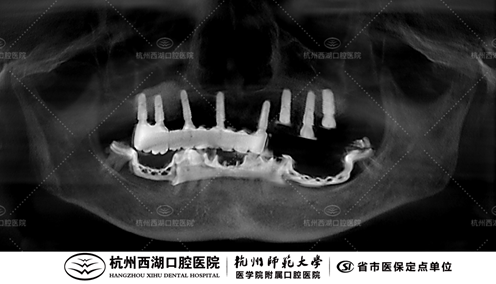

术前CBCT照如下